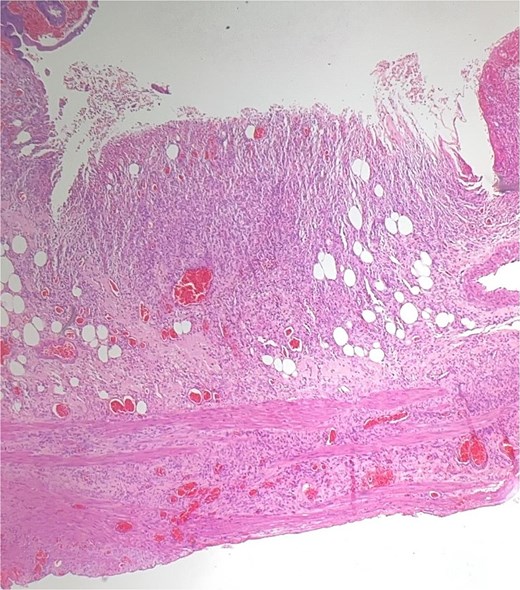

Histological evaluation confirmed acute necrotizing colitis with transmural inflammation and granulation tissue (Figs 4 and 5). Hepatic cyst biopsies revealed benign biliary duct cysts with cystically dilated bile ductules.

Histopathology: surface ulceration with perforation as indicated by fat lobules (arrow).